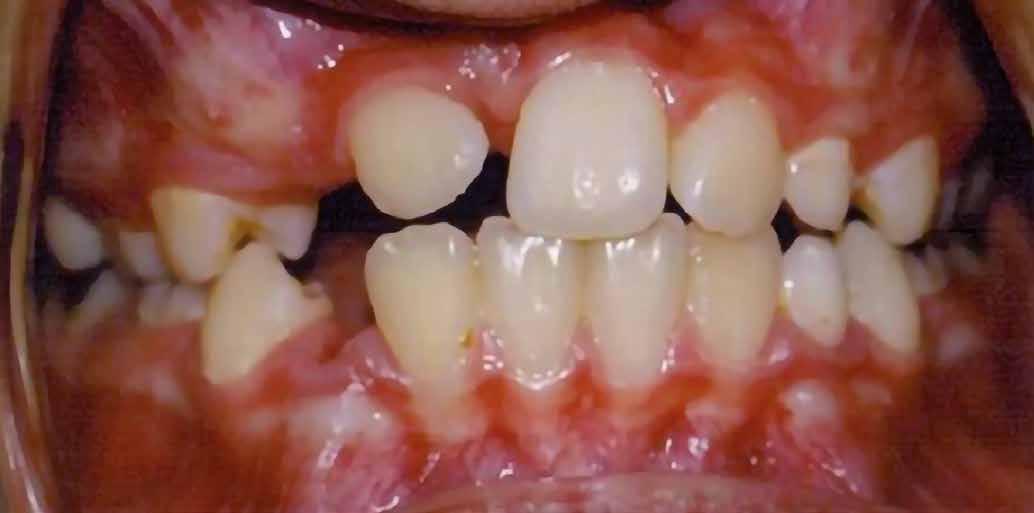

Már a vegyes fogazattal rendelkező páciensek körében is gyakran találkozhatunk impaktálódott fogakkal. Ebben a korban legtöbbször a felső metszőfogak impakcióját figyelhetjük meg. A frontfogak előtörése során előforduló diszkrepanciák a későbbiekben súlyos esztétikai problémák kialakulásához vezethetnek. Ennek a cikknek az a célja, hogy bemutassa egy impaktálódott felső középső metszőfog lézerrel asszisztált sebészi feltárását, továbbá az azt követő sikeres orthodonciai mozgatását. A cikknek ugyancsak célja, hogy felhívja a figyelmet az impaktálódott felső középső metszőfogak ellátásának fontosságára, valamint, hogy rámutasson a lézeres sebészi feltárásra, valamint a fogmozgatás gyorsaságára gyakorolt pozitív hatásaira.

A 10 éves férfi páciens a felső frontfogai késői/nem megvalósuló előtörése miatt kereste fel a rendelőnket. A klinikai és a radiológiai vizsgálat során a jobb felső nagymetszőfog impakcióját észleltük (1. ábra). A fog horizontális tengelyállással és dilacerált gyökérrel rendelkezett. A felső dentális középvonal a fogak vándorlása miatt jelentős mértékben elcsúszott. A bal felső kismetszőfog is rendkívül kedvezőtlen pozícióba került.

6 hónapon keresztül tartott. Ennek megfelelően a fog körül található szövetek a felszabadítás, valamint a havi kontrollok során 975 nm-es (több mint 25 J/cm2 energiasűrűség) és 660 nm-es hullámhosszúságú (12–18 J/cm2 energiasűrűség) lézersugarakkal is megvilágításra kerültek. Az impaktálódott fogat megközelítőleg 7 hónap alatt tudtuk megfelelő pozícióba mozgatni (3. ábra). Az orthodoncia kezelés aktív szakasza 18 hónapon keresztül tartott. A fogívek végső nivellálását és a fogak végleges pozícióba rendezését 0.018 × 0.025-ös acélívekkel végeztük.

A kezelés befejezésekor a páciens mosolya drámai mértékben javult, továbbá a frontfogak elhelyezkedése és az ínyszél lefutása is szemmel látható módon kedvezőbbé vált (4. ábra). A kezelés végén készült CBCT felvétel nem mutatta

Összefoglalás

A lágyrészekkel fedett fogak sebészi felszabadítása során alkalmazott lézerek, továbbá a fogmozgatás gyorsítására alkalmazott alacsony energiájú lézeres terápia kombinálása kedvező hatással lehet az impaktált fogak kezelése céljából alkalmazott terápia kimenetelére. Ez különös mértékben igaz lehet a dilacerált gyökerekkel rendelkező fogak esetében. Ez a megközelítés jelentősen javíthat az eset várható prognózisán. A kiegészítő kezelés révén a parodontális szö-

vetek egészsége, az okkluzális viszonyok minősége, valamint az esztétikai megjelenés is kedvezőbb lehet. Ez a hatás még látványosabb lehet fiatal páciensek esetében.